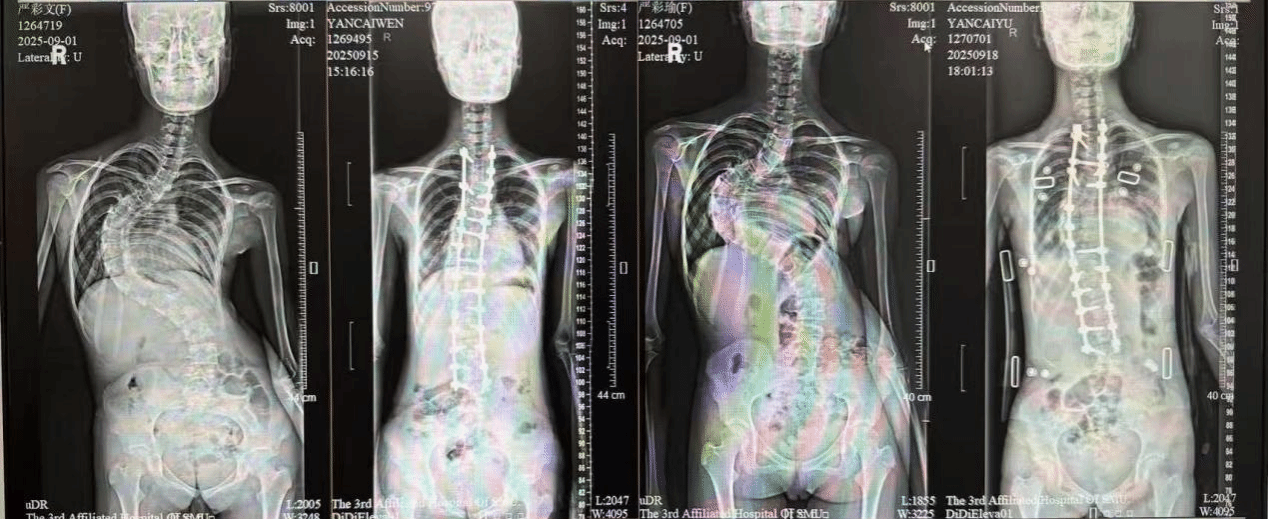

从“弯”到“直”:一场跨越110度的生命矫形

“真的很感谢医生和护士们,两个孩子现在终于能挺直腰板了。”在第三附属医院的骨科病房,一对双胞胎姐妹的母亲向医护人员表达感激。这对姐妹花因患有严重的脊柱侧弯,在这里先后接受了矫形手术,迎来人生新起点。这对来自偏远地区的双胞胎,从小就有脊柱弯曲的情况。由于早期当地医疗条件有限,她们未能及时接受系统规范的矫形治疗,尝试过一些非医学手段进行调理,但脊柱弯曲的问题并…